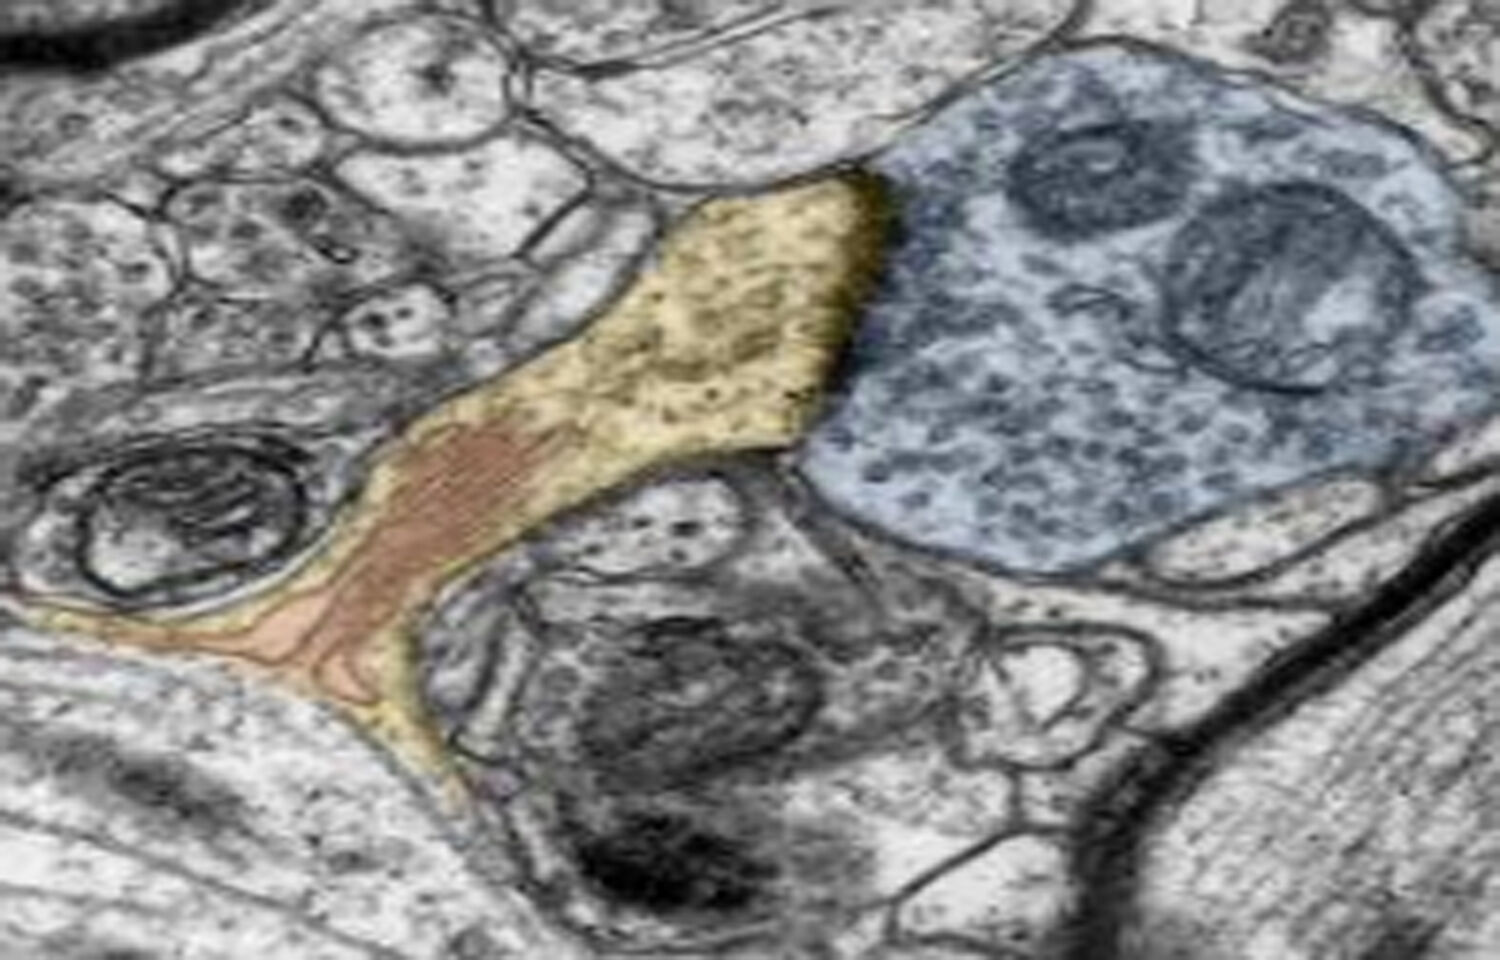

However, toxic vitamin A aggregates ("dimers") have been implicated in the pathophysiology of Stargardt and dry-AMD. Vitamin A dimers form when two molecules of vitamin A are combined. Specifically, ALK-001 is vitamin A modified by replacing hydrogen with deuterium, a stable, non-radioactive isotope of hydrogen. Substituting vitamin A with ALK-001 safely slows the rate of formation of vitamin A dimers and prevents the disease in mice.

ALK-001 is a form of vitamin A that has been chemically-modified to slow the formation of toxic vitamin A dimers in the eye and is usually consumed once a day orally.